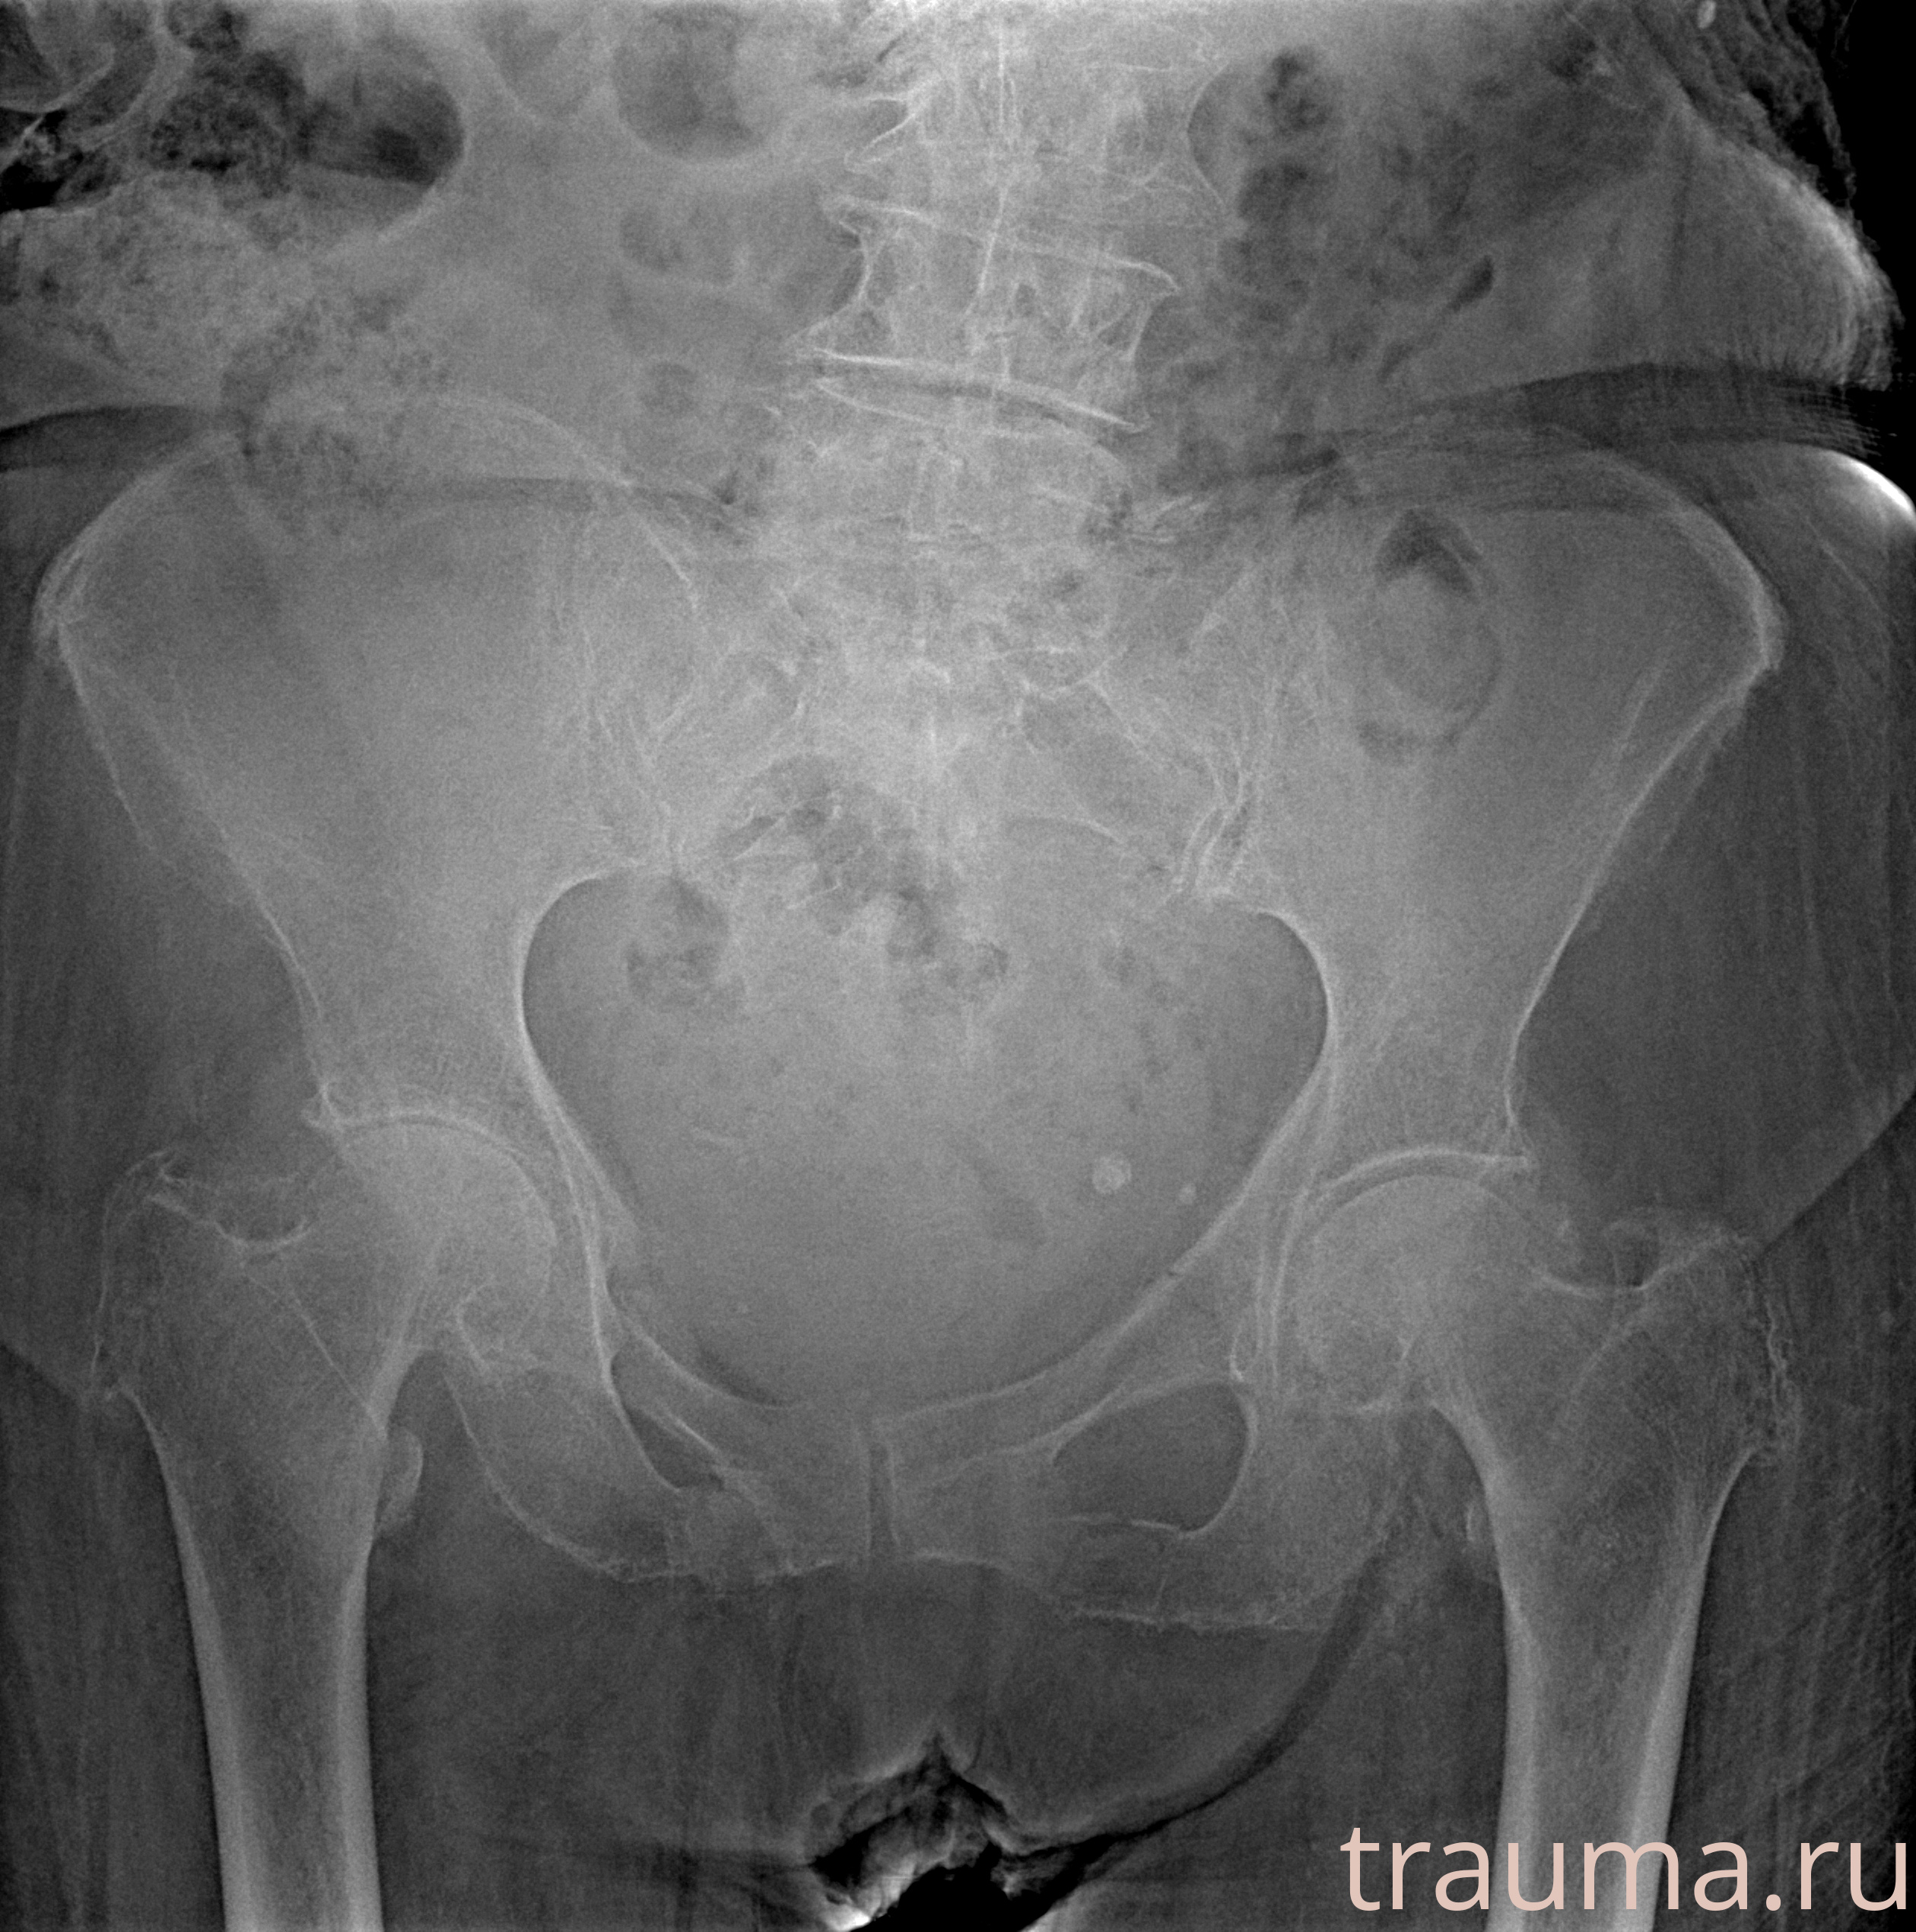

Рентгенограммы

Рентген на дому: по вашему адресу приезжает врач-рентгенолог, травматолог-ортопед с мобильным рентгеновским аппаратом, проводит диагностику травмы или заболевания, делает необходимые рентгенограммы, дает рекомендации по дальнейшему лечению. Получить качественные снимки в домашних условиях возможно благодаря уникальной методике, разработанной МосРентген Центром для института  Склифосовского